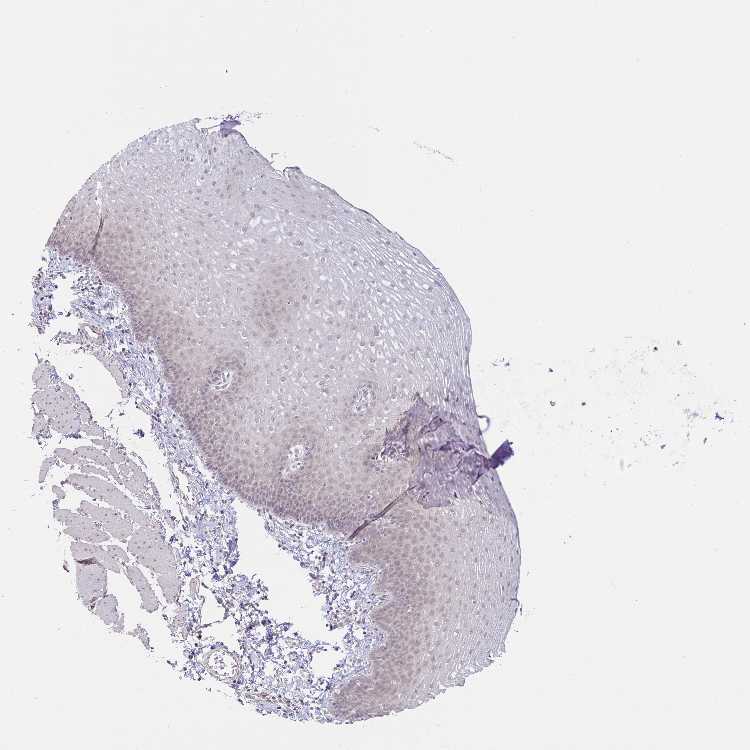

ESOPHAGUS - Antibody stainingi

Antibody staining in the annotated cell types in the current human tissue is reported as not detected, low, medium, or high, based on conventional immunohistochemistry profiling in selected tissues. This score is based on the combination of the staining intensity and fraction of stained cells.

Each image is clickable and will lead to virtual microscopy that enables deeper exploration of all samples and also displays staining intensity scores, fraction scores and subcellular localization as well as patient and tissue information for each sample.

Antibody HPA055252

Squamous epithelial cells Not detected